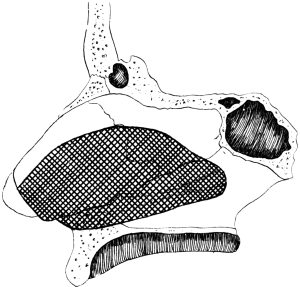

| 310. | Semi-diagrammatic Transverse Section of the Nose | 610 |